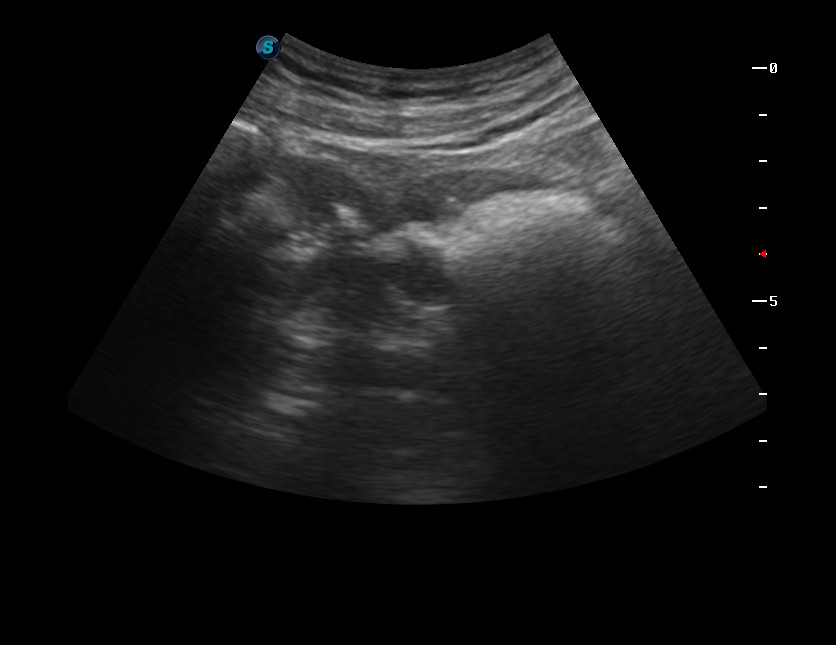

Дедушка 90 лет. Профилактическое обследование.

Выявлен сегмент толстой кишки с неравномерно утолщенными стенками.

После дообследование выполнена резекция толстой кишки, диагноз аденокарциномы подтвержден морфологически.